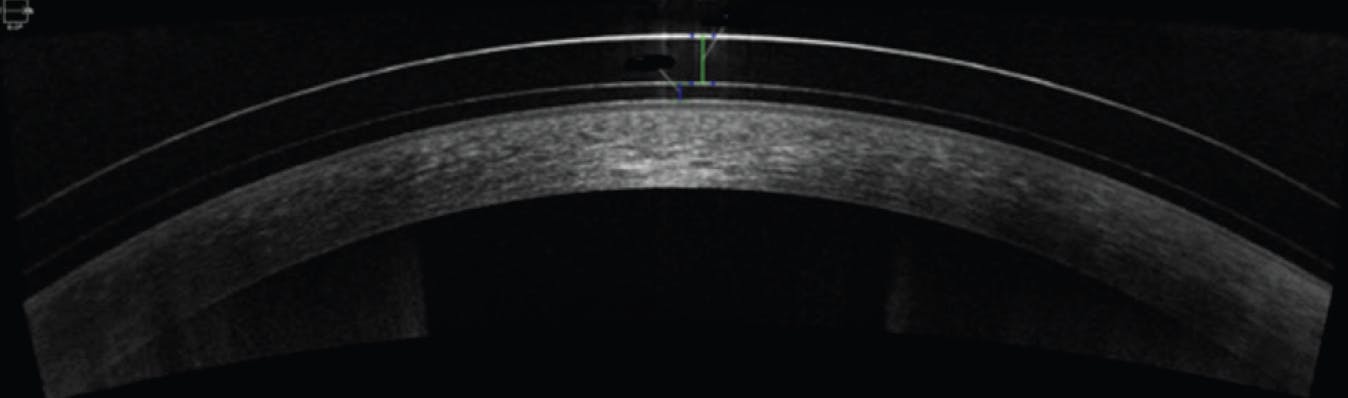

Lens Clearance

Adequate central lens clearance also varies according to the lens manufacturer and design (Figure 2). The number of microns recommended for central clearance is usually provided by the lens fitting guide. The minimal central clearance is desired to keep lens and corneal interaction at a minimum and increase oxygen transmissibility. Excessive central clearance can cause increased pressure on the lens haptics, resulting in a more difficult peripheral landing zone fitting.